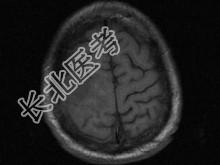

单项选择题男,63岁, 反复抽搐30余年加重伴左侧肢体活动不利活1月余,PE: 右顶部约4cm×5cm大小隆起包块质硬,不能活动, 右上下肢肌力Ⅴ,左上下肢肌力Ⅳ+, 根据所提供图像,最可能的诊断为 ( )

A、右顶骨(副脊索瘤)或称为肌上皮瘤

B、右顶骨转移瘤

C、右顶骨骨瘤

D、右顶骨血管瘤

E、右顶骨胆脂瘤